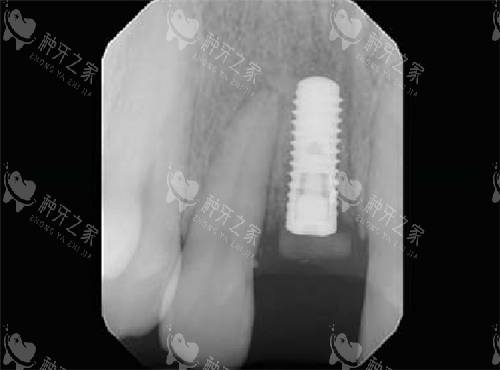

瑞士士卓曼iti种植牙植入后